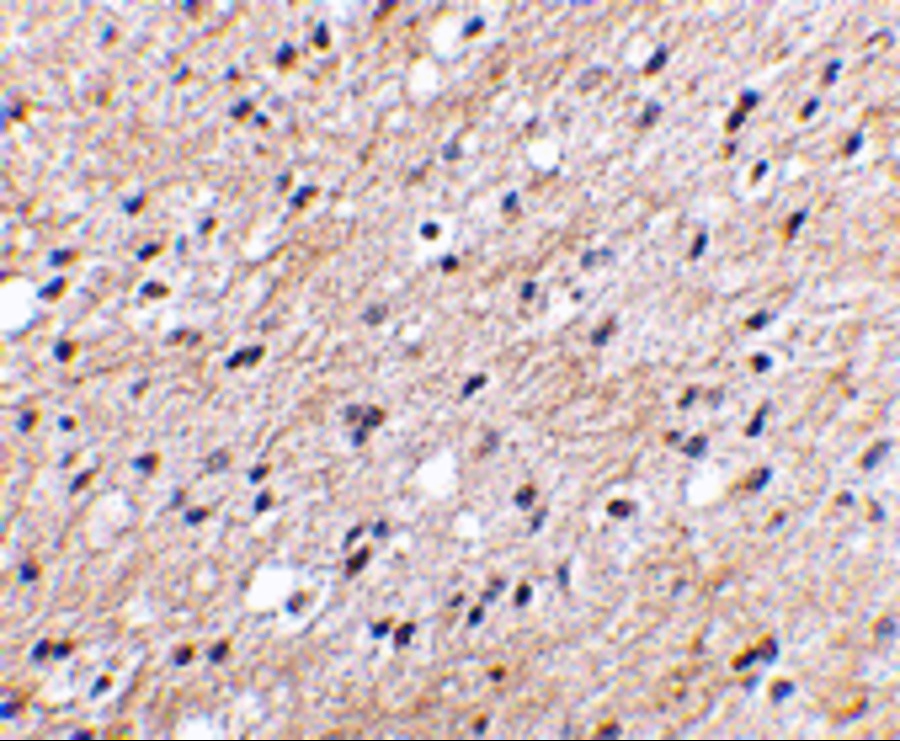

- Immunohistochemistry (IHC)